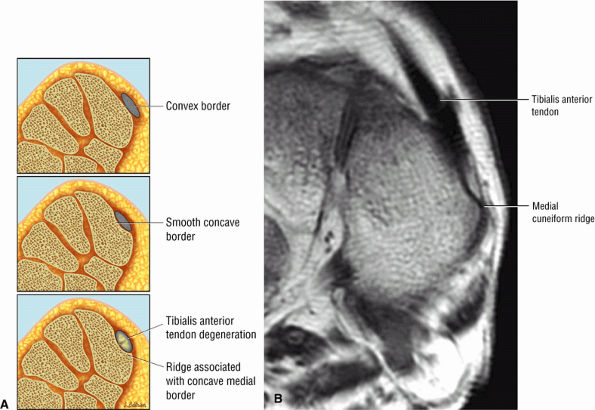

-

Tibialis anterior (the most likely of the extensor tendons to tear)

Peroneus tertius

associated with a convex appearance to the tendon anteriorly, as well as tendon thickening and often increased intrasubstance signal. Tears and tendinosis suspected in the sagittal plane are confirmed and further characterized in the axial plane.